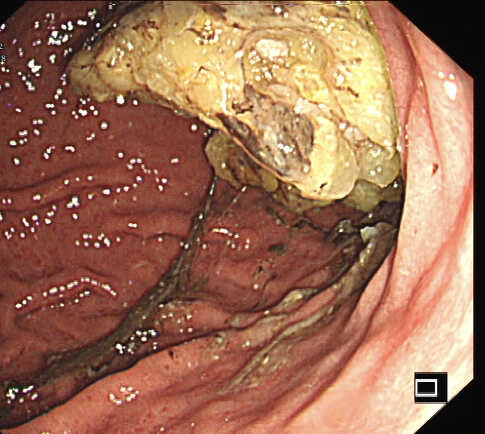

胃镜证实